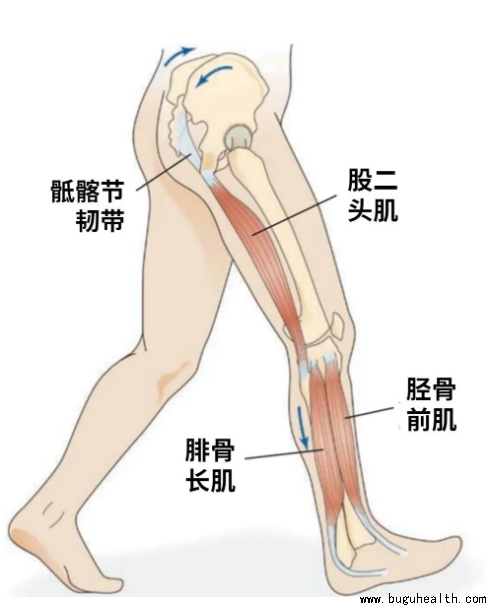

- 布骨医学科普:韧带有没有弹性,能不能拉长? BuGuRMC布骨康复医疗中心 ,2023-11-22

- 韧带属于一种致密的结缔组织,在微观上它和肌腱大体相似,主要由大量Ⅰ型胶原纤维构成。不过在结构上它们也会存在一些差异,比如肌腱的胶原纤维走向是平行排列的,因为它要传递肌肉产生的力;而韧带需要抵抗多个方向的力,所以它的纤维对线在结构上各不相同。.....